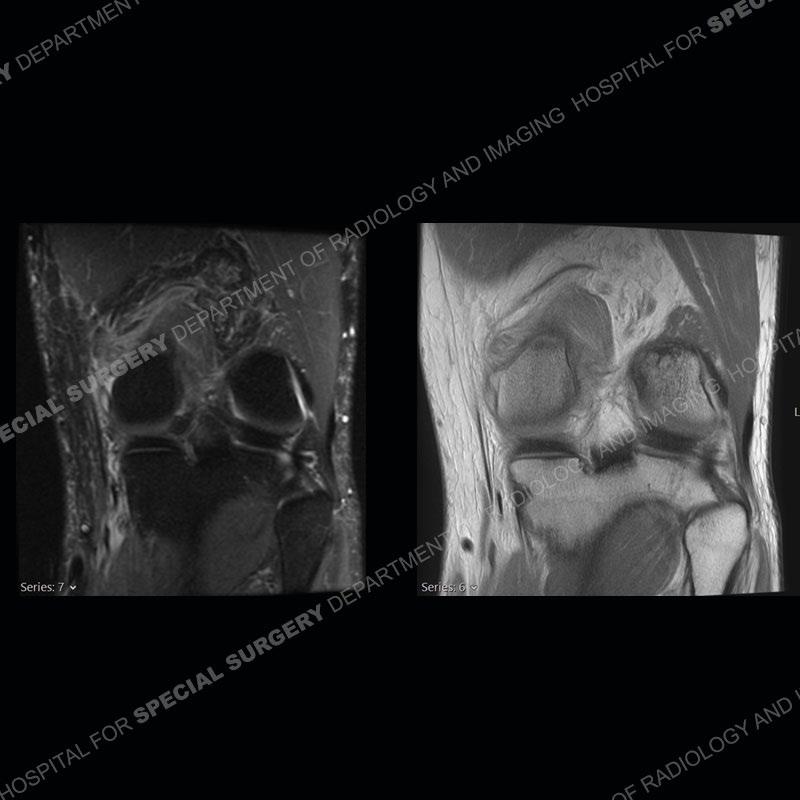

Findings

The radiographs show degenerative change of the medial compartment and a varus knee, but they are not germane to this case. No acute bony injury is present. The MRI shows edema of the posterior medial knee/soft tissue and a focal area of a partially disrupted low signal structure. The details are kept at a minimum in the findings of this case on purpose.

Diagnosis: Partial Disruption Medial Head Gastrocnemius (MHG)

The findings were kept purposefully vague as identifying the structures early on takes away a lot of the diagnosis. An uncommon entity and one of which we do not see a lot. Enthesopathic changes and tendinosis are seen as are distal MHG injuries, but proximal tears are rarely present. This case highlights a number of points. One, it almost always comes down to anatomy. Perhaps not a structure we normally spend too much time on, except save for diagnosing a Baker’s cyst, but knowing where this structure and all structures exist in all three planes is imperative. Second, when you think you are making a “call” or finding that you have never made before, step back and think is this just the abnormal presentation of a common pathology. That situation arises much more frequently. Third, if you look at it once, twice, and probably a third time and are confident in your odd or very rare diagnosis, stick to your guns. Especially, when it comes down to anatomic structures, the proof will be in the images.

Fourth, use all imaging planes and different pulse sequences to make your diagnosis. The edema highlighted in this case can be seen as the obscuration of fat on the PD images but is much easier to perceive as the high signal on the IR pulse sequences. The actual disruption of the MHG myotendinous junction is only able to be seen on the axial images. On the sagittal and coronal images, we get a sense something is wrong but hard to be exact. Lastly, when you look at a study and something just seems off (as I would say the sagittal and coronal images do with that dark band of tissue posteriorly), listen to yourself and go through the study slowly and meticulously. Most of the time you will find you were right, and something indeed is present.